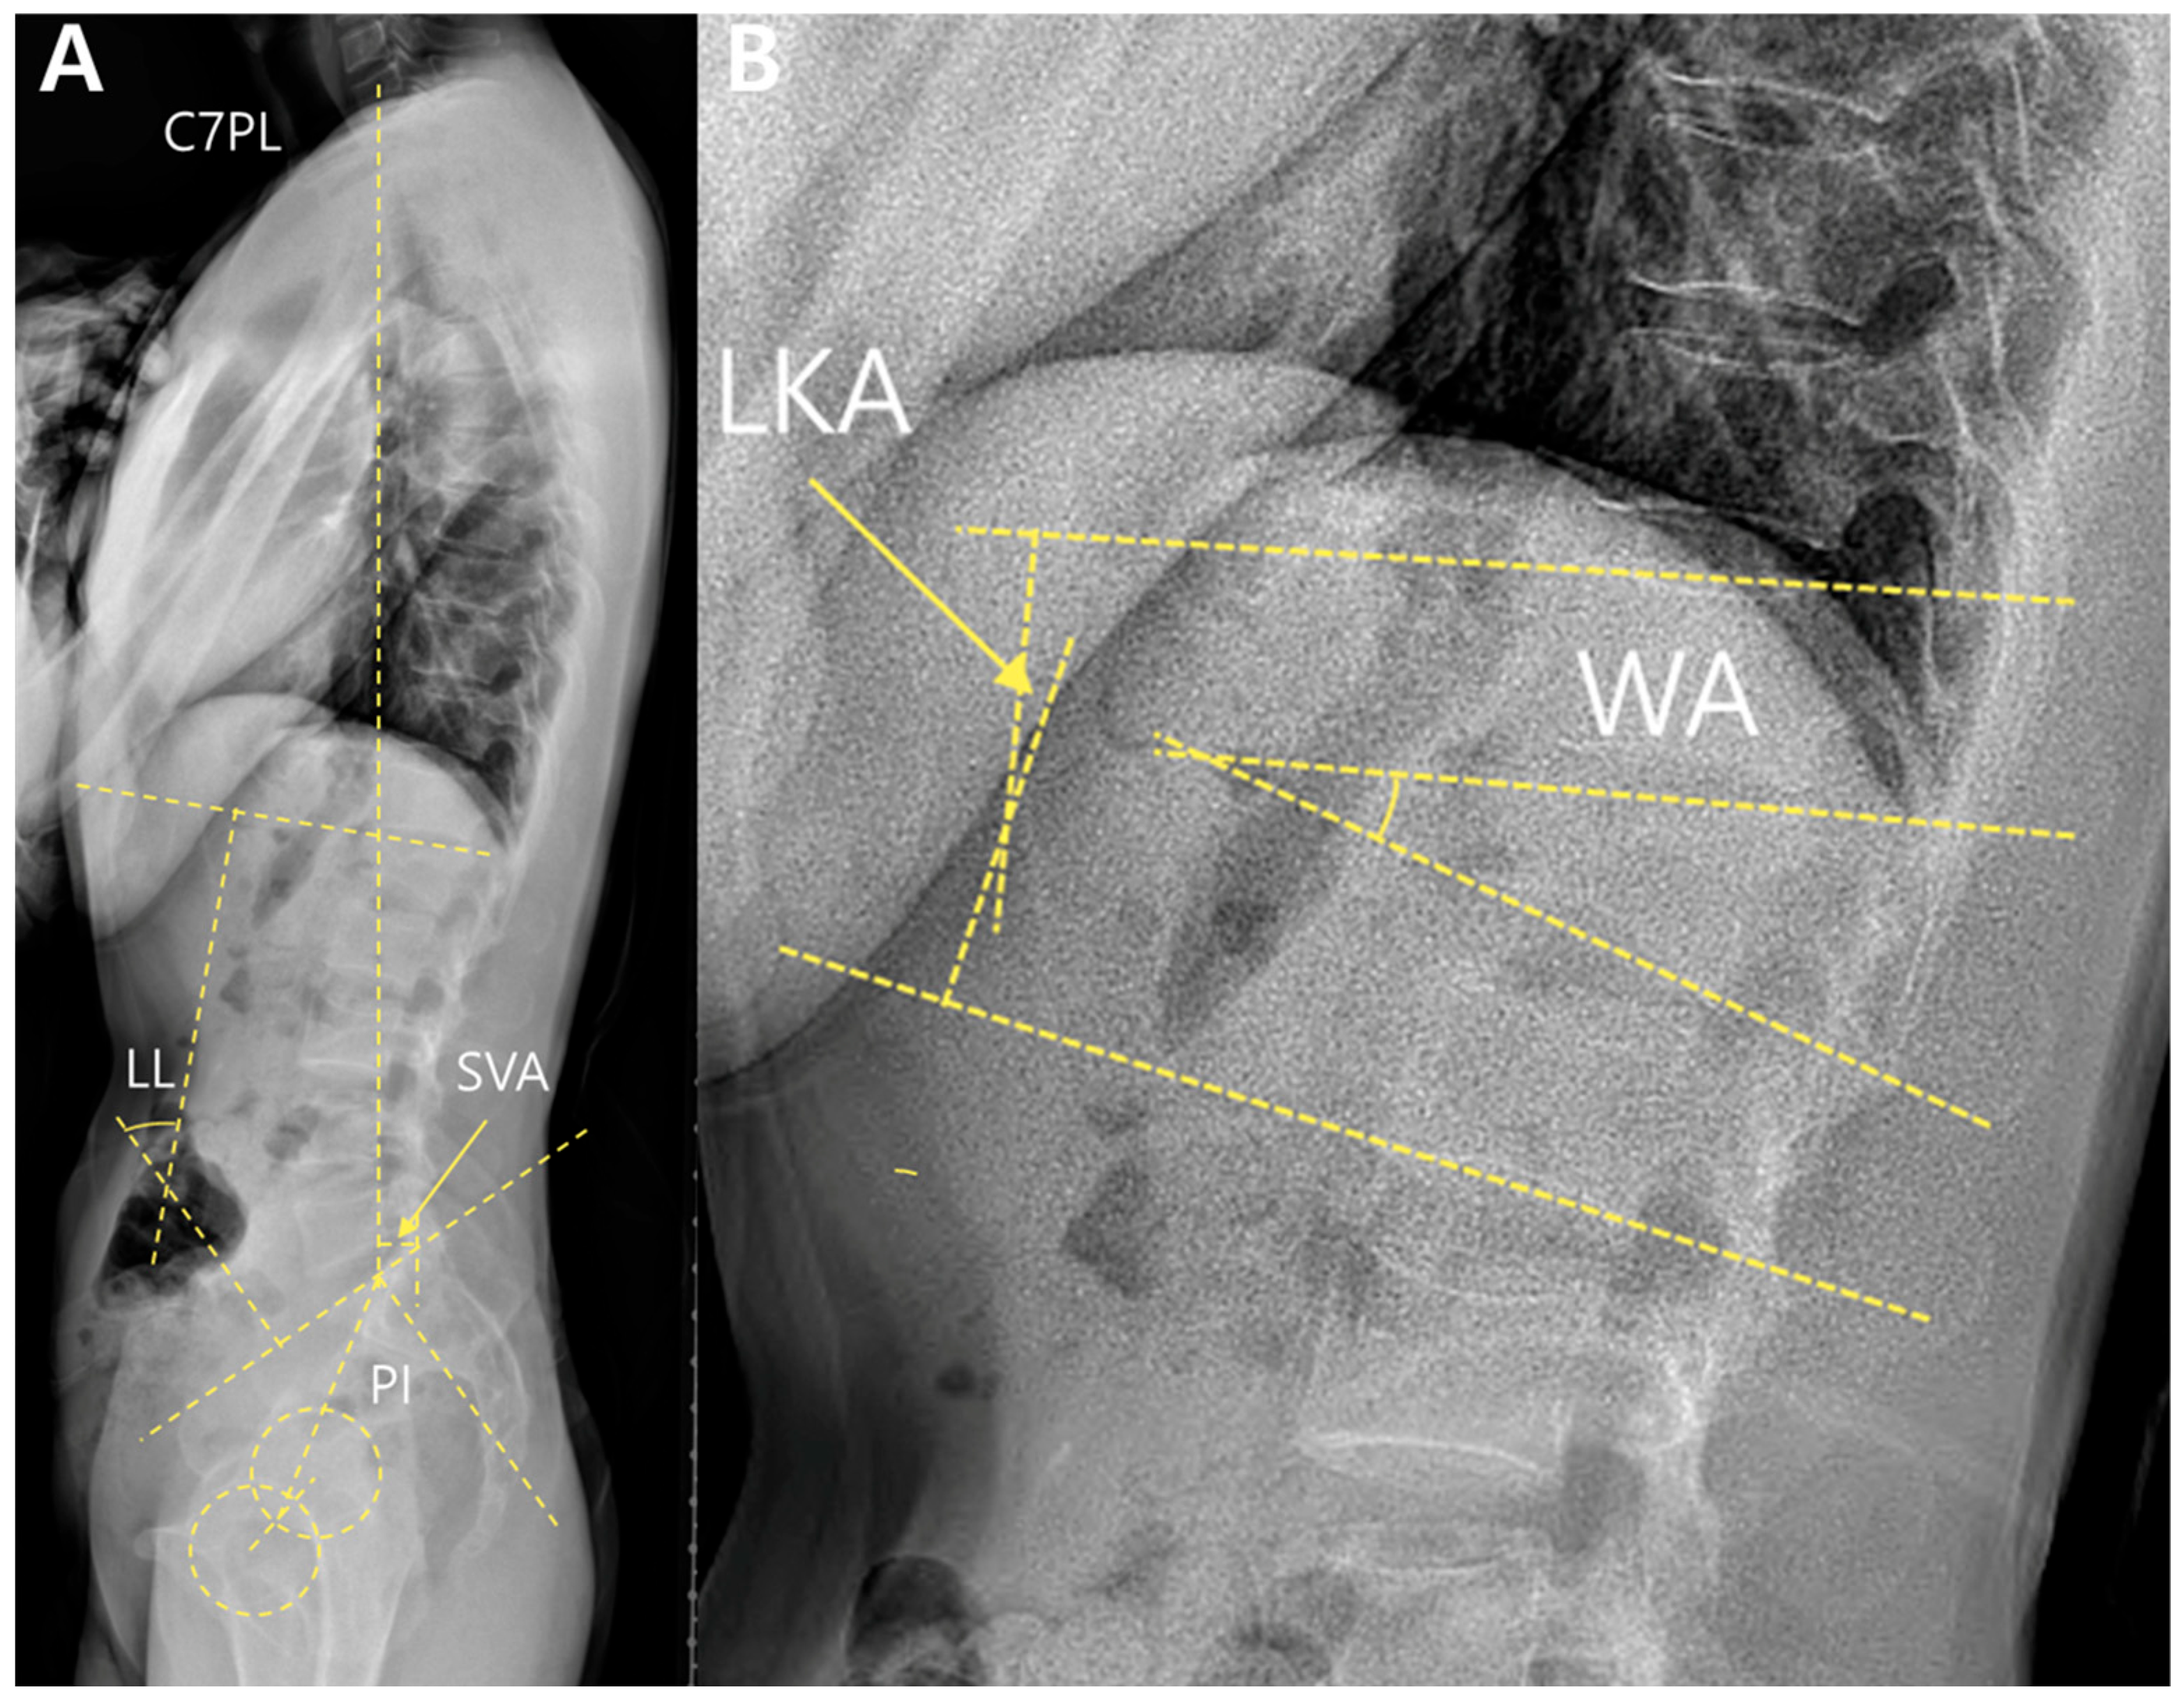

Local alignment included the local kyphotic angle (LKA) and wedge angles (WA). These were measured using standing whole-spine lateral radiographs (Figure 2).

The LKA was defined as the angle between the superior endplate of the vertebra above and the inferior endplate of the vertebra below the fractured segment. The WA was measured between the upper and lower endplates of the fractured vertebrae.

Global alignment parameters included the sagittal vertical axis (SVA), lumbar lordosis (LL), pelvic incidence (PI), and PI–LL mismatch. The SVA was defined as the horizontal distance between the C7 plumb line and the posterosuperior corner of the S1 endplate. LL was measured as the angle between the superior endplates of L1 and S1. PI is defined as the angle between the line perpendicular to the sacral endplate and the line connecting the midpoint of the sacral endplate to the femoral head axis. The PI–LL mismatch was calculated by subtracting LL from PI.

Figure 2. Measurements of spinal parameters. (A) Standing whole-spine lateral radiograph of a patient with an L1 burst fracture; (B) Magnified lateral view at the fracture level. The wedge angle (WA) was measured between the upper and lower endplates of the fractured vertebra, and the local kyphotic angle (LKA) was measured between the superior endplate of the vertebra above and the inferior endplate of the vertebra below. Abbreviations: C7PL, C7 plumb line; SVA, sagittal vertical axis; LL, lumbar lordosis; PI, pelvic incidence; WA, wedge angle; LKA, local kyphotic angle.